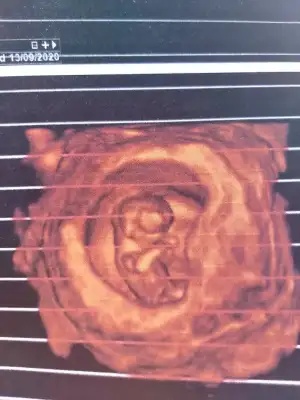

Erkek gibi ama emin olamadım usg net değil başka varsa usg paylaşınSevgili arkadaşlar bize de bakabilir misiniz?12 haftaligiz.Bir kızım var 5 yaşında.İkinci olacakEki Görüntüle 2597265

merhaba biz hala burdayizNet olmamakla birlikte kız gibi başka usg varsa paylaşın yada 12+ usg paylaşın

merhaba biz hala burdayizve kesin olarak cinsiyet öğrenemedik son resmimiz bir tahmin yapılabilinirmi

Merhabalar tekrar bugün doktora gittim yüzde 80 kız dedi sevgiliIkra meyra

Nubu görünmüyor diger usgden emin değilim yazmıştım başka usg varsa paylaşınMerhabalar tekrar bugün doktora gittim yüzde 80 kız dedi

Net değil usg puslanıyor yakınlaşınca sanki emin degilim kız gibi varsa usg paylaşınIkra meyra Merhabaa 10 haftalik usg ye kiz demistin simdi 12. haftadayiz doktor goremedim dedi tekrar bakar misin :)

Bugün 15+6 olduk sevgiliNubu görünmüyor diger usgden emin değilim yazmıştım başka usg varsa paylaşınkaç haftalık usg

Maalesef elimde bunlardan başka usg yok yorumlarınız için teşekkür ederim son kez bakabilir misiniz rica etsem?kız olursada tabiiki sağlıklı hayırlı evlat olsun çok seviniriz.Ama insan illa ki değişik olsun istiyor

3 usg kaç haftalık nubu dik görünüyor ne bilim cnm dr daha detaylı bakıyor hatta çizeyimMaalesef elimde bunlardan başka usg yok yorumlarınız için teşekkür ederim son kez bakabilir misiniz rica etsem?kız olursada tabiiki sağlıklı hayırlı evlat olsun çok seviniriz.Ama insan illa ki değişik olsun istiyorIkra meyra